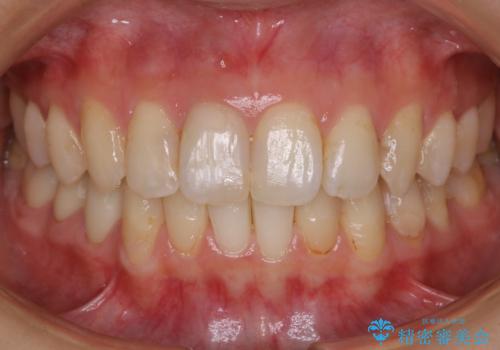

- 前歯のガタつきと噛み合わせの改善を希望してご来院されました。

目立たない装置での矯正治療をとのことでインビザラインを用いた非抜歯矯正を行うこととなりました。